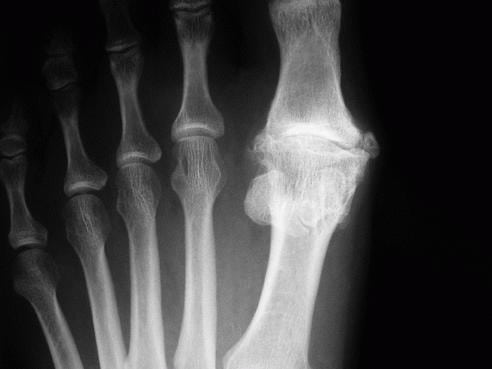

При диагностировании воспаления сустава большого пальца на ноге врачи чаще всего предполагают, что его причиной стал артрит. Это заболевание развивается из-за нарушения обмена веществ, травмирования сочленения, проникновения в него инфекционных возбудителей. Самая опасная разновидность патологии — ревматоидный артрит. В основе его патогенеза лежит неправильная реакция иммунной системы на собственные клетки организма. К довольно редким формам заболевания относится псориатический артрит. Его обнаружение обычно не вызывает трудностей — боли в большом пальце ноги сопровождаются формированием на коже характерных папул и бляшек. Какие симптомы указывают на развитие артрита:

Эта патология дегенеративно-дистрофического характера протекает на фоне постепенного разрушения сустава. Часто затрагивает самые крупные сочленения (тазобедренное, локтевое), но по мере прогрессирования поражает и мелкие суставы. Артроз, в отличие от артрита, не относится к воспалительным заболеваниям. Патология может развиться в результате повреждения синовиальной сумки или инфицирования синовиальной жидкости. На то, что воспалились суставы на пальцах ног, указывают следующие признаки:

Подагра — ревматическое заболевание, одна из форм артрита. Патология часто поражает мелкие суставы, провоцируя воспаление. Ее причиной становится нарушение обмена веществ — пуринов. В суставах накапливаются кристаллы солей мочевой кислоты, раздражающие ткани, вызывающие их изменения. Это становится толчком к развитию острого воспаления сустава большого пальца ноги. Он сильно отекает, краснеет из-за гиперемии кожи в зоне поражения. Возникают «дергающие» острые боли, интенсивность которых нарастает. Они могут исчезать через несколько дней, а затем появляться при очередном рецидиве. Чем лечить воспаление сустава большого пальца на ноге:

Если суставы на пальцах ног воспалились, то врач при пальпации нередко обнаруживает плотное компактное уплотнение. Оно немного смещается при нажатии, а пациент при этом жалуется на болезненные ощущения. Такое уплотнение — характерный признак бурсита, или воспаления синовиальной сумки, не распространяющегося на рядом расположенные структуры. Причинами заболевания могут стать избыточные нагрузки, вальгусная деформация стопы, артриты, травмирование, инфекции и даже переохлаждение. Палец немного отекает, увеличивается в размерах по сравнению со здоровым, а кожа над уплотнением становится гладкой, ровной. В начале лечения врач делает пункцию, удаляя из синовиальной сумки скопившийся экссудат. Биологический образец направляется в лабораторию для исследования. При выявлении инфекционной природы бурсита пациенту проводится антибиотикотерапия. В лечении используются НПВП в таблетках и мазях. После купирования воспаления могут быть назначены наружные средства с разогревающим действием: